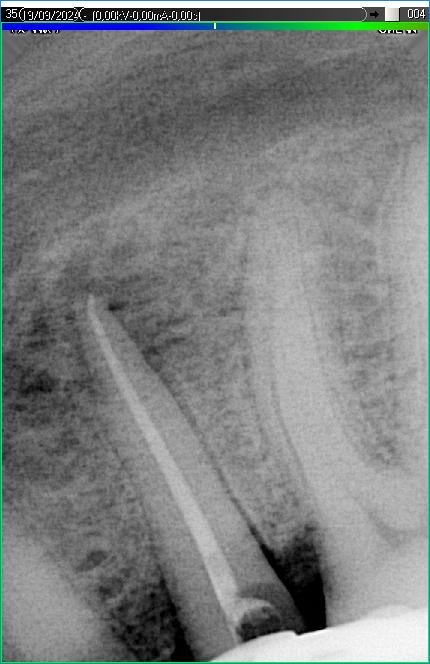

Вилучення інструменту з каналів зуба